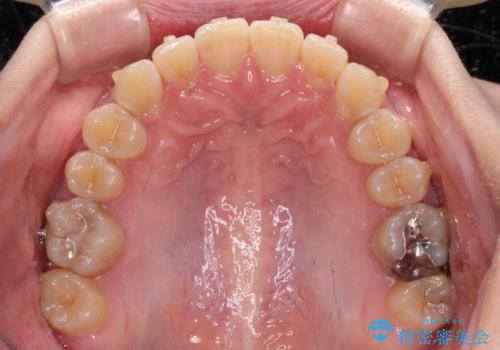

- 下顎の八重歯を気にして来院された患者様です。

マウスピース矯正でもワイヤー矯正でも対応可能であり、マウスピースによる治療を希望されたため、インビザラインを用いることとしました。

下顎前歯にデコボコが集中していたため、顎間ゴムによる後方移動とIPR(歯と歯の間を削ること)により歯列を整えることとしました。

下顎前歯のデコボコが集中しており、奥歯の咬み合わせは、上顎に対して下顎が前方位にある状態でした。下顎の歯列を後方へ移動させる治療はインビザラインの得意とするところですので、1年程度で無事に治療を終えることができました。